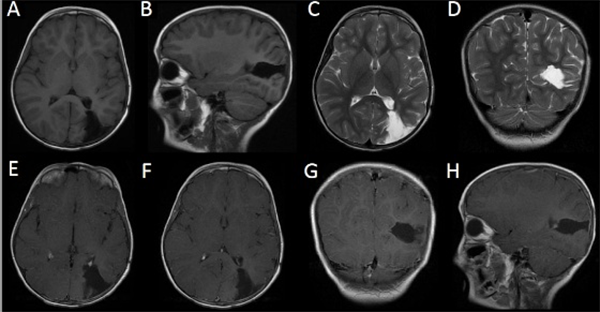

La tomografía computada (TC) de encéfalo sin contrate reveló una lesión isodensa respecto al parénquima cerebral, subcortical parieto-occipital izquierda, asociada a edema perilesional. La resonancia magnética nuclear (RMN) de encéfalo, con y sin contraste, evidenció una lesión sólida, parieto-occipital izquierda isointensa con la sustancia gris en T1 y de intensidad heterogénea en T2 con un gran edema asociado que, tras la administración de contraste, presenta un marcado realce homogéneo, sin restricción en la difusión (Figura 1).

Figura 1: RMN. Lesión sólida parietooccipital izquierda isointensa en T1 y heterointensa con gran edema perilesional en T2. Marcado refuerzo post contraste, sin difusión.